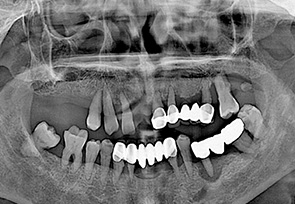

전악 임플란트는 치아가 완전히 없는 상태라도 잇몸뼈가 남아 있다면 임플란트를 여러개 심어 고정식으로 이를 해 넣을 수 있습니다. 잇몸 뼈에 단단히 고정되는 임플란트를 이용한 치료법으로 틀니를 사용할 때 보다 힘이 훨씬 좋고 내 치아 처럼 사용할 수 있습니다. 자연치아는 모두 28개 이지만 실직적으로 자연치아 개수만큼 다 심을 필요는 없습니다. 고정성 전악 임플란트를 위해서는 위 아래 턱 뼈와 맞물리게 되는 치아의 상태와 잇몸 뼈의 상태 등을 고려하여 임플란트를 식립하게 되며 보통 아래는 6~7개, 위에는 7~8개의 임플란트를 식립한 후 고정식으로 보철물을 결합하게 됩니다.

현재 치아의 상태를 정확하게 검진하는 것이 매우 중요합니다. 치아가 소실 된 시간이 오래될 수록 잇몸 뼈의 소실량이 많아지기 때문에 임플란트를 식립할 수 있는 잇몸뼈의 양과 질을 철저하게 분석하는 것이 매우 중요합니다.